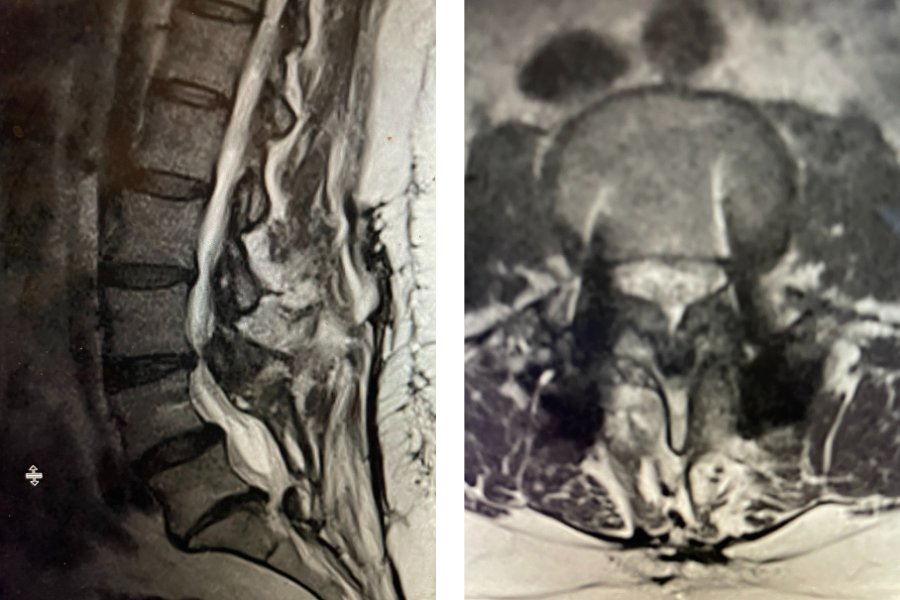

After 25 years in practice, I still find it challenging, but quite rewarding: removing degenerative material off the dural membrane in the lumbar spine. Some people […]